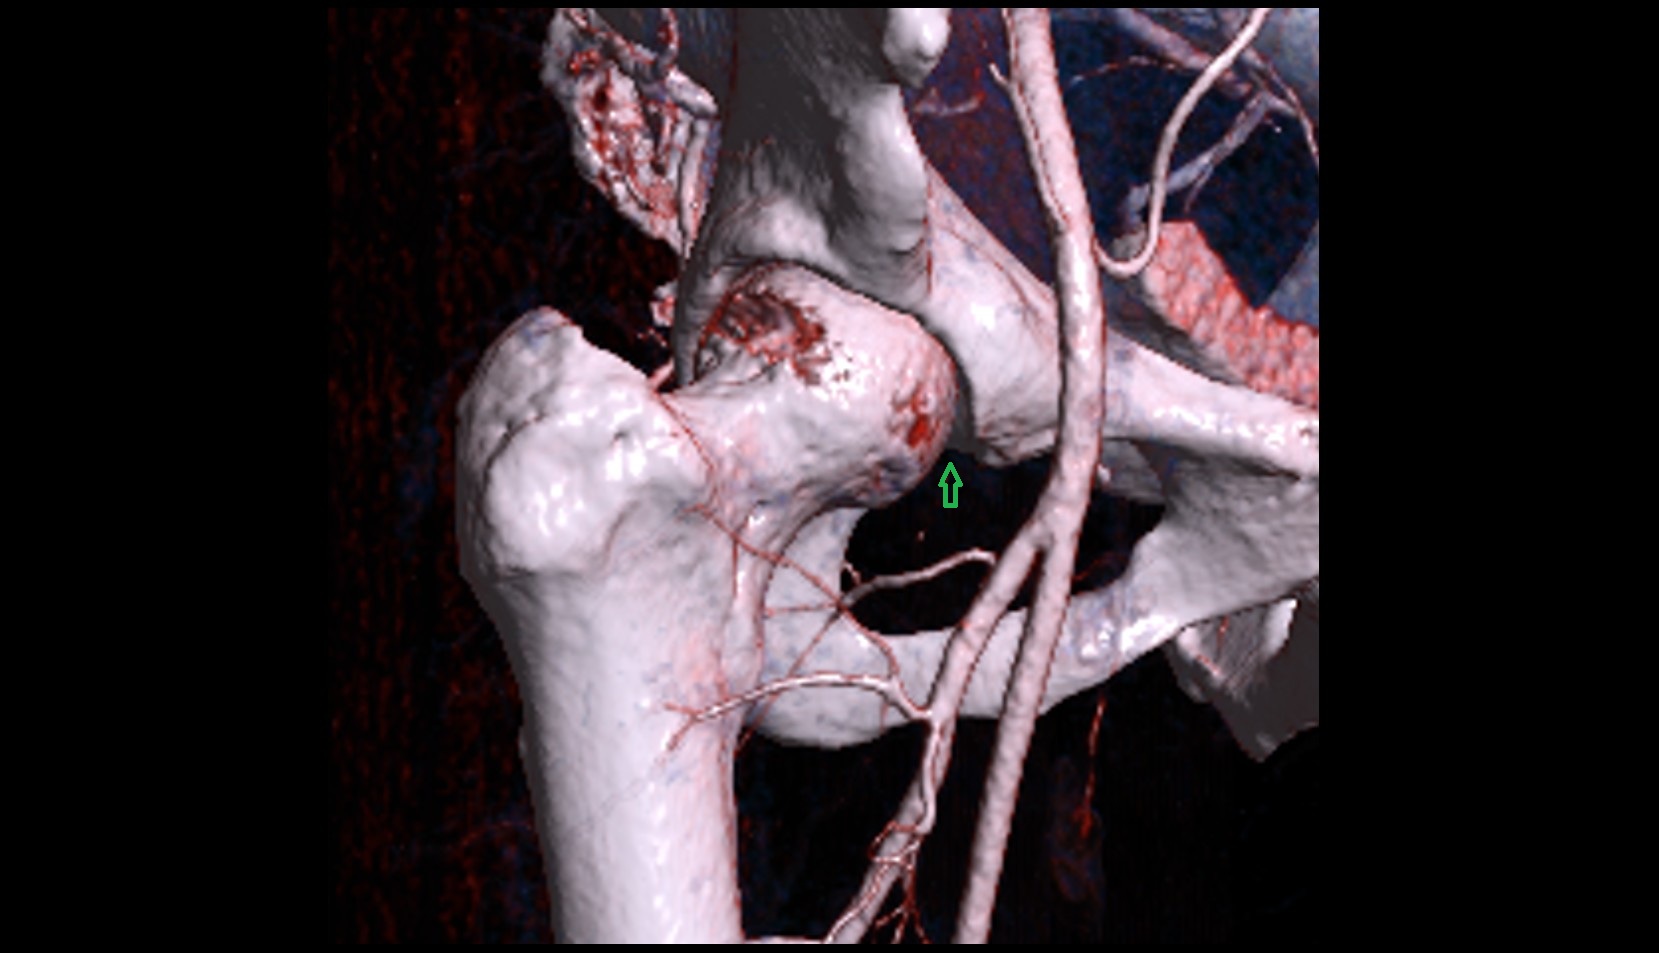

- Head of femur

- Neck of femur

- Lateral circumflex femoral artery

- Deep femoral artery (profunda femoris)

- External iliac artery

- Femoral artery

- Internal iliac artery

- Medial circumflex femoral artery

- Obturator artery